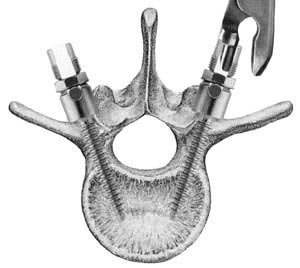

Seeing The Screws

Spinal fusion

is the most widely performed surgery for scoliosis. In this procedure, bone (either harvested from elsewhere in the body (autograft), or donor bone (allograft) is

grafted

to the vertebrae so that when it heals, they will form one solid bone mass and the

vertebral column

becomes rigid.

This prevents worsening of the curve at the expense of spinal movement.

This can be performed from the anterior (front) aspect of the spine by entering the

thoracic

or

abdominal cavity

, or performed from the back (posterior). A combination of both is used in more severe cases.

sagittal

imbalance and rotational defects unresolved by the Harrington rod system. They involve a combination of rods, screws, hooks and wires fixing the spine and can apply stronger, safer forces to the spine than the Harrington rod. Spinal fusion is rarely performed without this instrumentation.